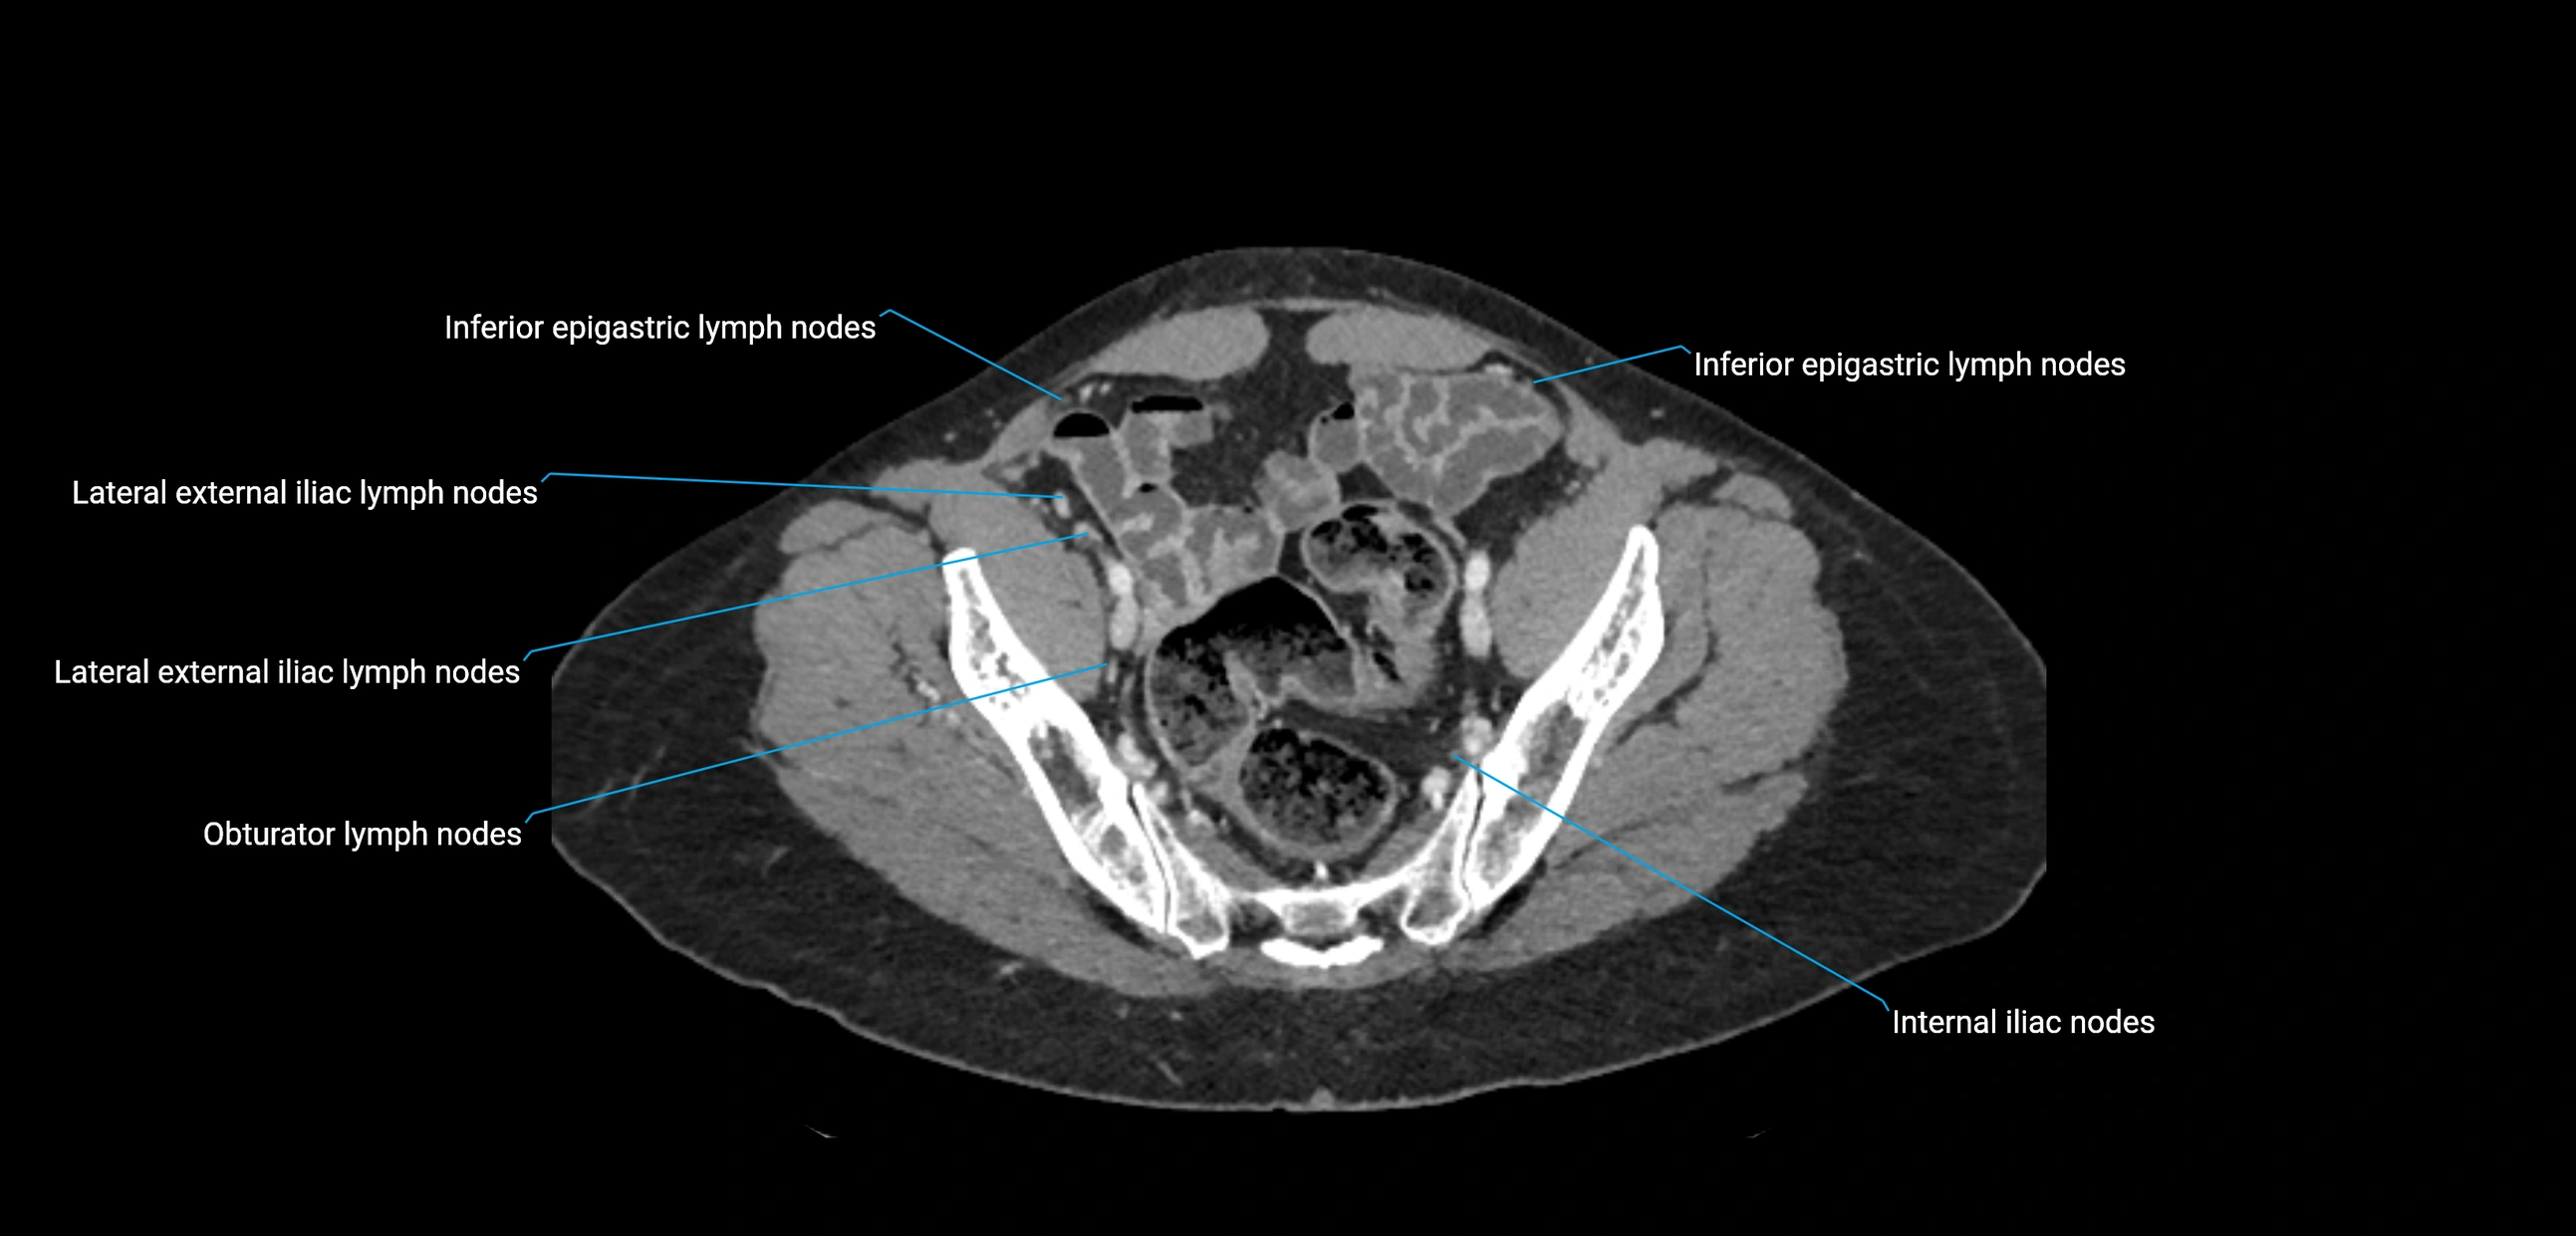

CT Appearance

CT Pre-Contrast:

• Nodes appear as soft-tissue density nodules adjacent to the aorta and IVC

CT Post-Contrast:

• Normal nodes enhance homogeneously

• Malignant nodes may show heterogeneous enhancement, central necrosis, or conglomerate formation

• Size >1 cm short axis is suspicious, though morphology and distribution are equally important

CT Venography (CTV):

• Demonstrates nodal encasement or compression of adjacent vessels (aorta, IVC, renal veins)